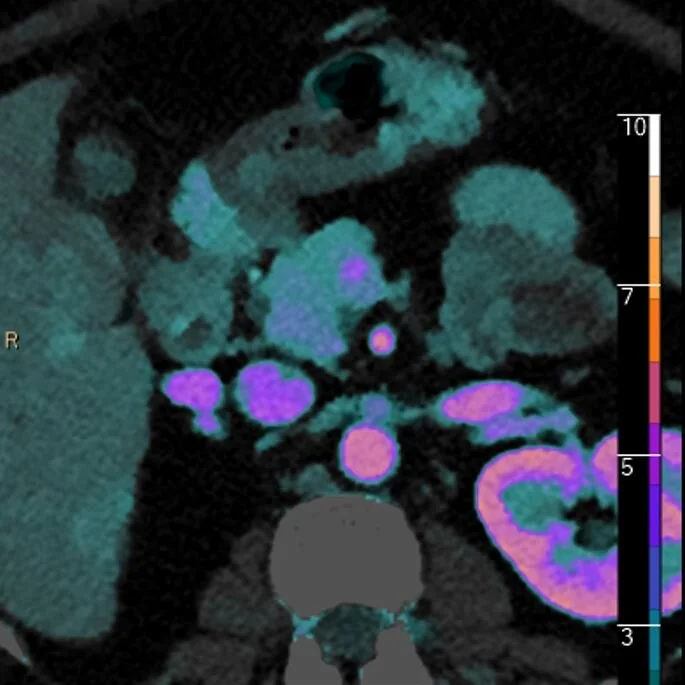

Roses and islet cells